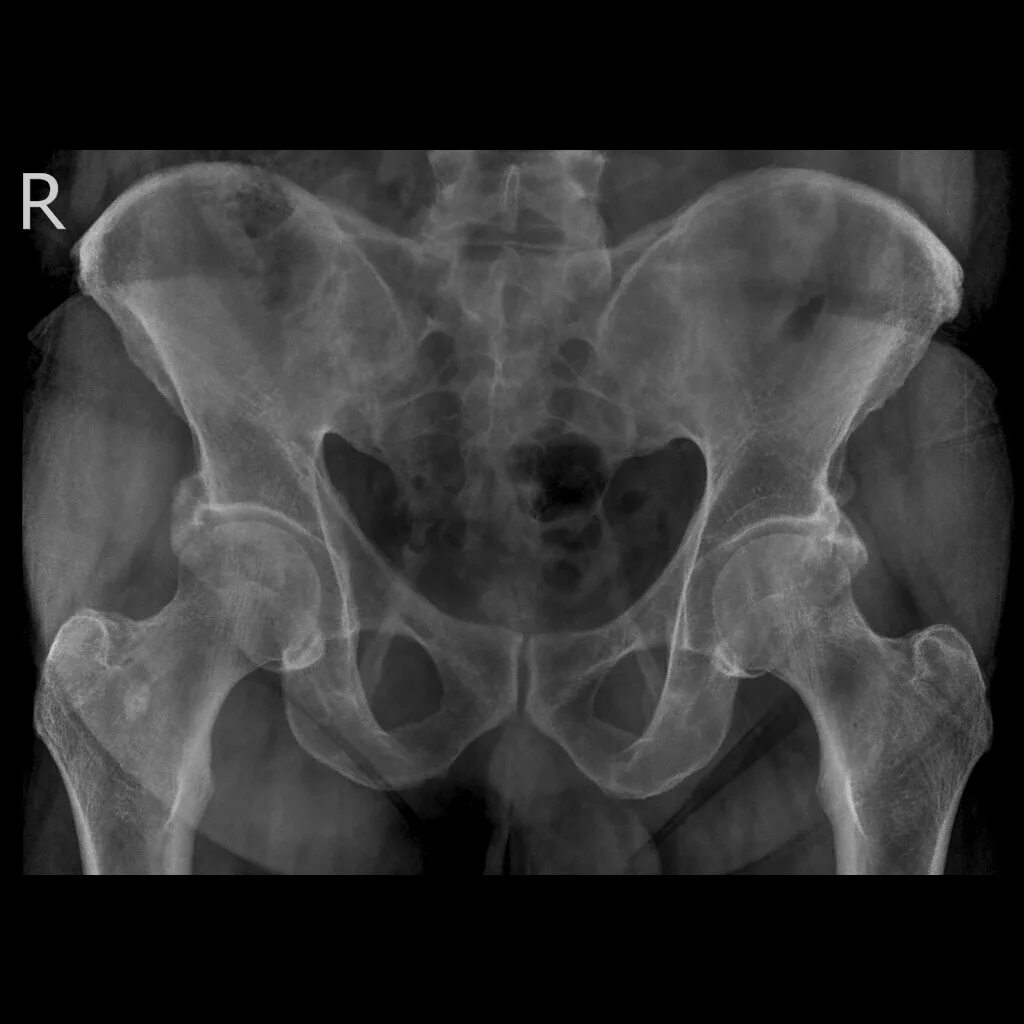

Артрит крестцово подвздошного сочленения